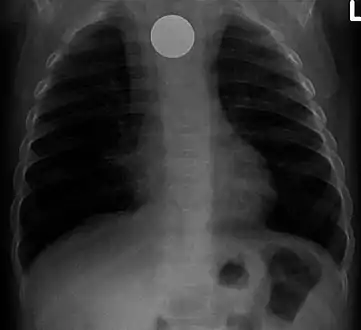

- A coin seen on AP CXR in the esophagus

- Multiple button batteries in the stomach